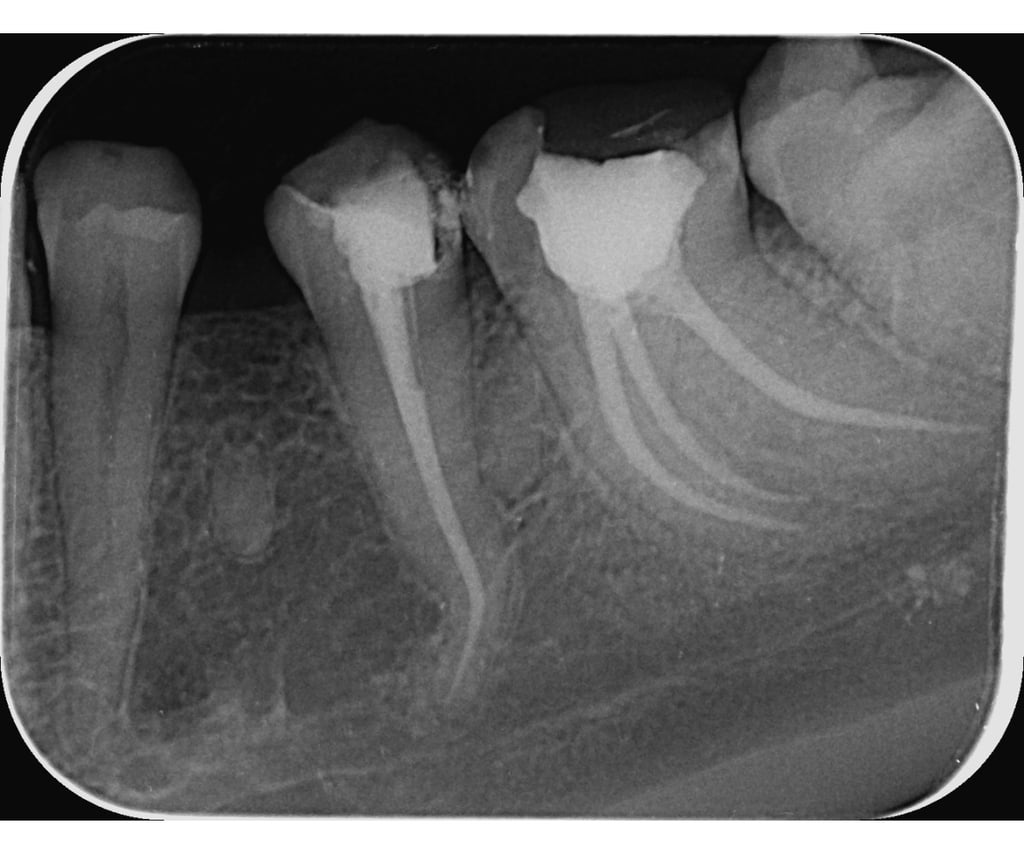

Endodontska terapija, se fokusira na lečenje unutrašnjosti zuba, posebno kanala korena. Savremeni standardi u ovoj oblasti uključuju korišćenje naprednih mašinskih instrumenata, što poboljšava preciznost i efikasnost tretmana.

Mašinska obrada korenovih kanala uključuje upotreba rotacionih ili reciprocirajućih mašina omogućava brže i efikasnije uklanjanje inficiranog tkiva i oblikovanje kanala.

Biokompatibilni materijali: Savremeni materijali za punjenje kanala, kao što su gutaperka ili bioceramika, poboljšavaju dugotrajnost i uspešnost terapije.